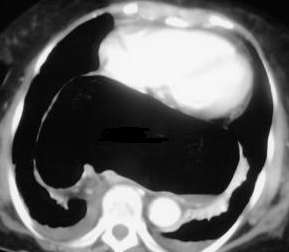

Different views of a double contrast-enhanced CT scan showing a left diaphragmatic hernia with an acute dilated stomach (Courtesy Dr. V. Penopoulos)